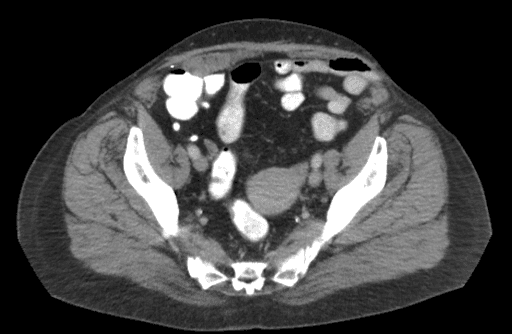

रोगी के जटिल ऑपरेटिव इतिहास के कारण, सर्जिकल हस्तक्षेप के साथ आगे बढ़ने से पहले क्रॉस-अनुभागीय इमेजिंग को अनिवार्य माना जाता था। सीटी स्कैन (चित्रा 1) पर, बाएं निचले चतुर्थांश पार्श्व में बाएं रेक्टस मांसपेशी में एक आंशिक-मोटाई चीरा हर्निया का सबूत है, जिसमें ट्रांसवर्सस एब्डोमिनिस (टीए) और आंतरिक तिरछा का विघटन होता है, जिसमें एक अक्षुण्ण बाहरी तिरछा होता है। विशेष रूप से उल्लेखनीय बाएं आंतरिक तिरछे पर आंत्र की उपस्थिति है। इस हर्निया के स्थान और आकार को देखते हुए, इसे ईएचएस वर्गीकरण का उपयोग करके L3W2 हर्निया माना जाएगा। इसके अतिरिक्त, रोगी की मिडलाइन में ऑनले जाल और बाईं ओर रोगी के गोल लिगामेंट से सटे एक वसा प्लग का प्रमाण है, जो अप्रत्यक्ष हर्निया घटक की उपस्थिति का संकेत देता है।

चित्र 1. इस रोगी के सीटी पेट श्रोणि का अक्षीय दृश्य एक बाएं निचले चतुर्थांश आंशिक-मोटाई चीरा हर्निया का प्रदर्शन करता है। बाएं आंतरिक तिरछे और ट्रांसवर्सस एब्डोमिनिस के पृथक्करण का प्रमाण है अर्धचंद्र रेखा पार्श्व के स्तर पर रेक्टस मांसपेशी के लिए एक अक्षुण्ण अतिव्यापी बाहरी तिरछा के साथ, एक आंशिक-मोटाई हर्निया के अनुरूप।